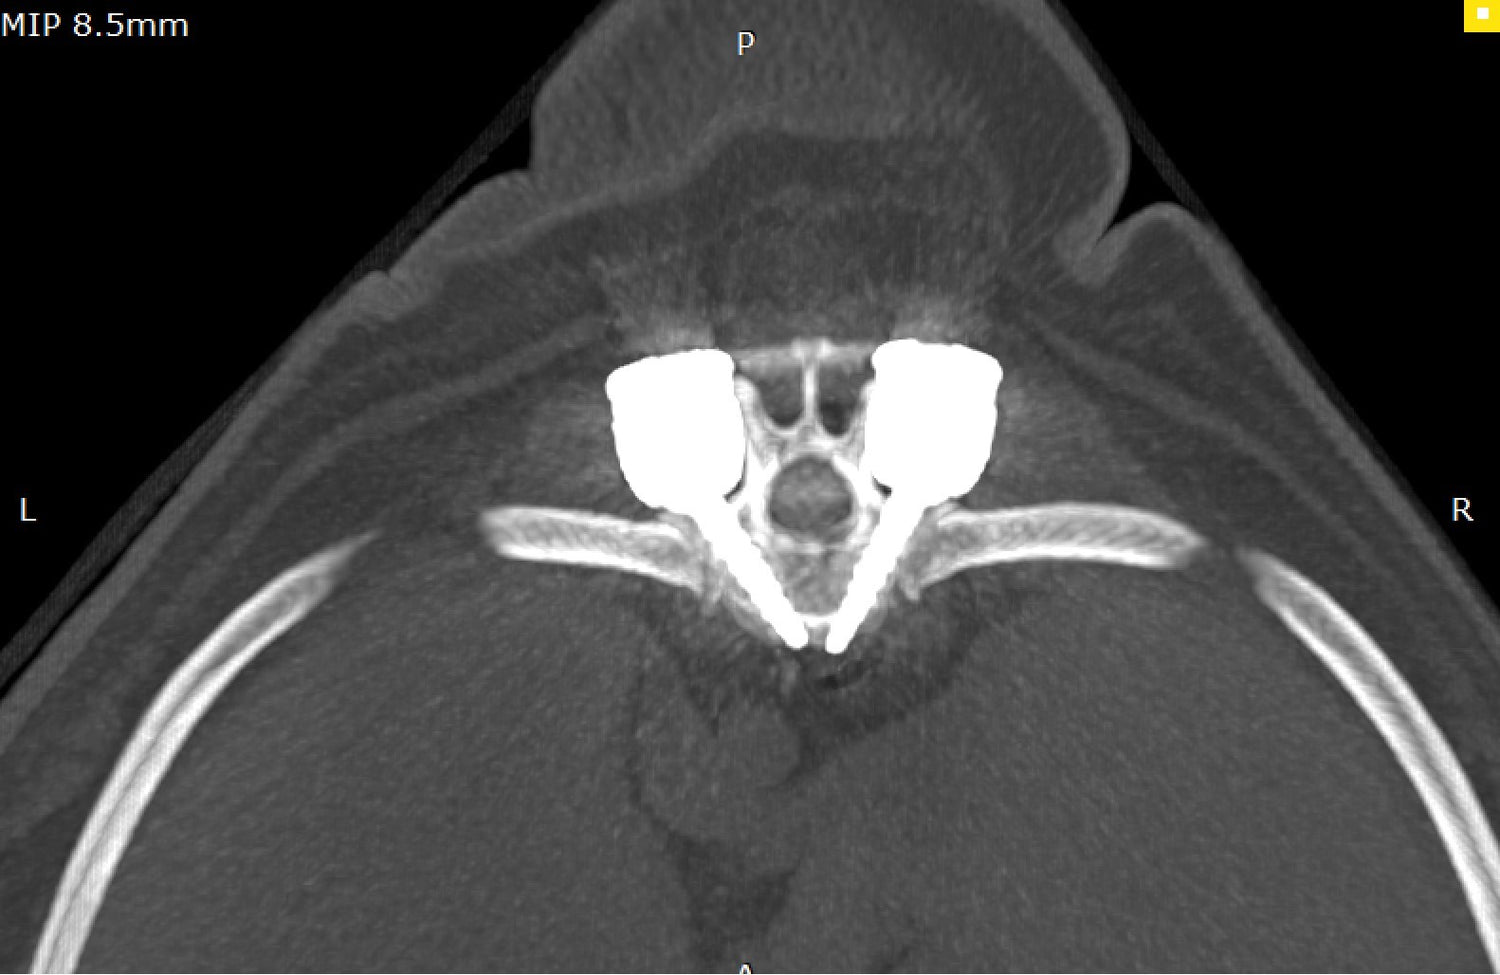

• Polyaxial screws with ball design with multiple degrees of freedom to increase screw placement options and allows placement in many different fashions

• System consists of screws, caps and rods

// User Cases

Highlighting the cases of these products in real-life situations is vital to demonstrating their success. Below are cases studies of long-term follow up surgeries.